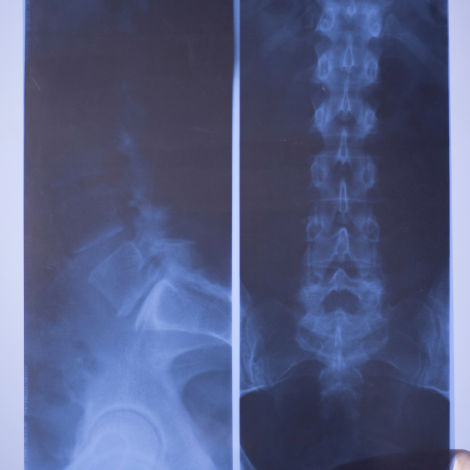

Lumbar Spine X-ray

It can help your doctor understand the cause of chronic back pain or view the effects of injuries, disease, or infection. Your doctor might prescribe a lumbar spine X-ray to diagnose: birth defects that affect the spine; injury or fractures to the lower spine; low back pain that’s severe or lasts for more than four to eight weeks.